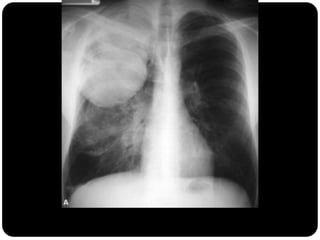

Massas

 São lesões com as mesmas características atribuídas aos

nódulos, porém com mais de 3cm de diâmetro.

Grande massa no lobo superior direito